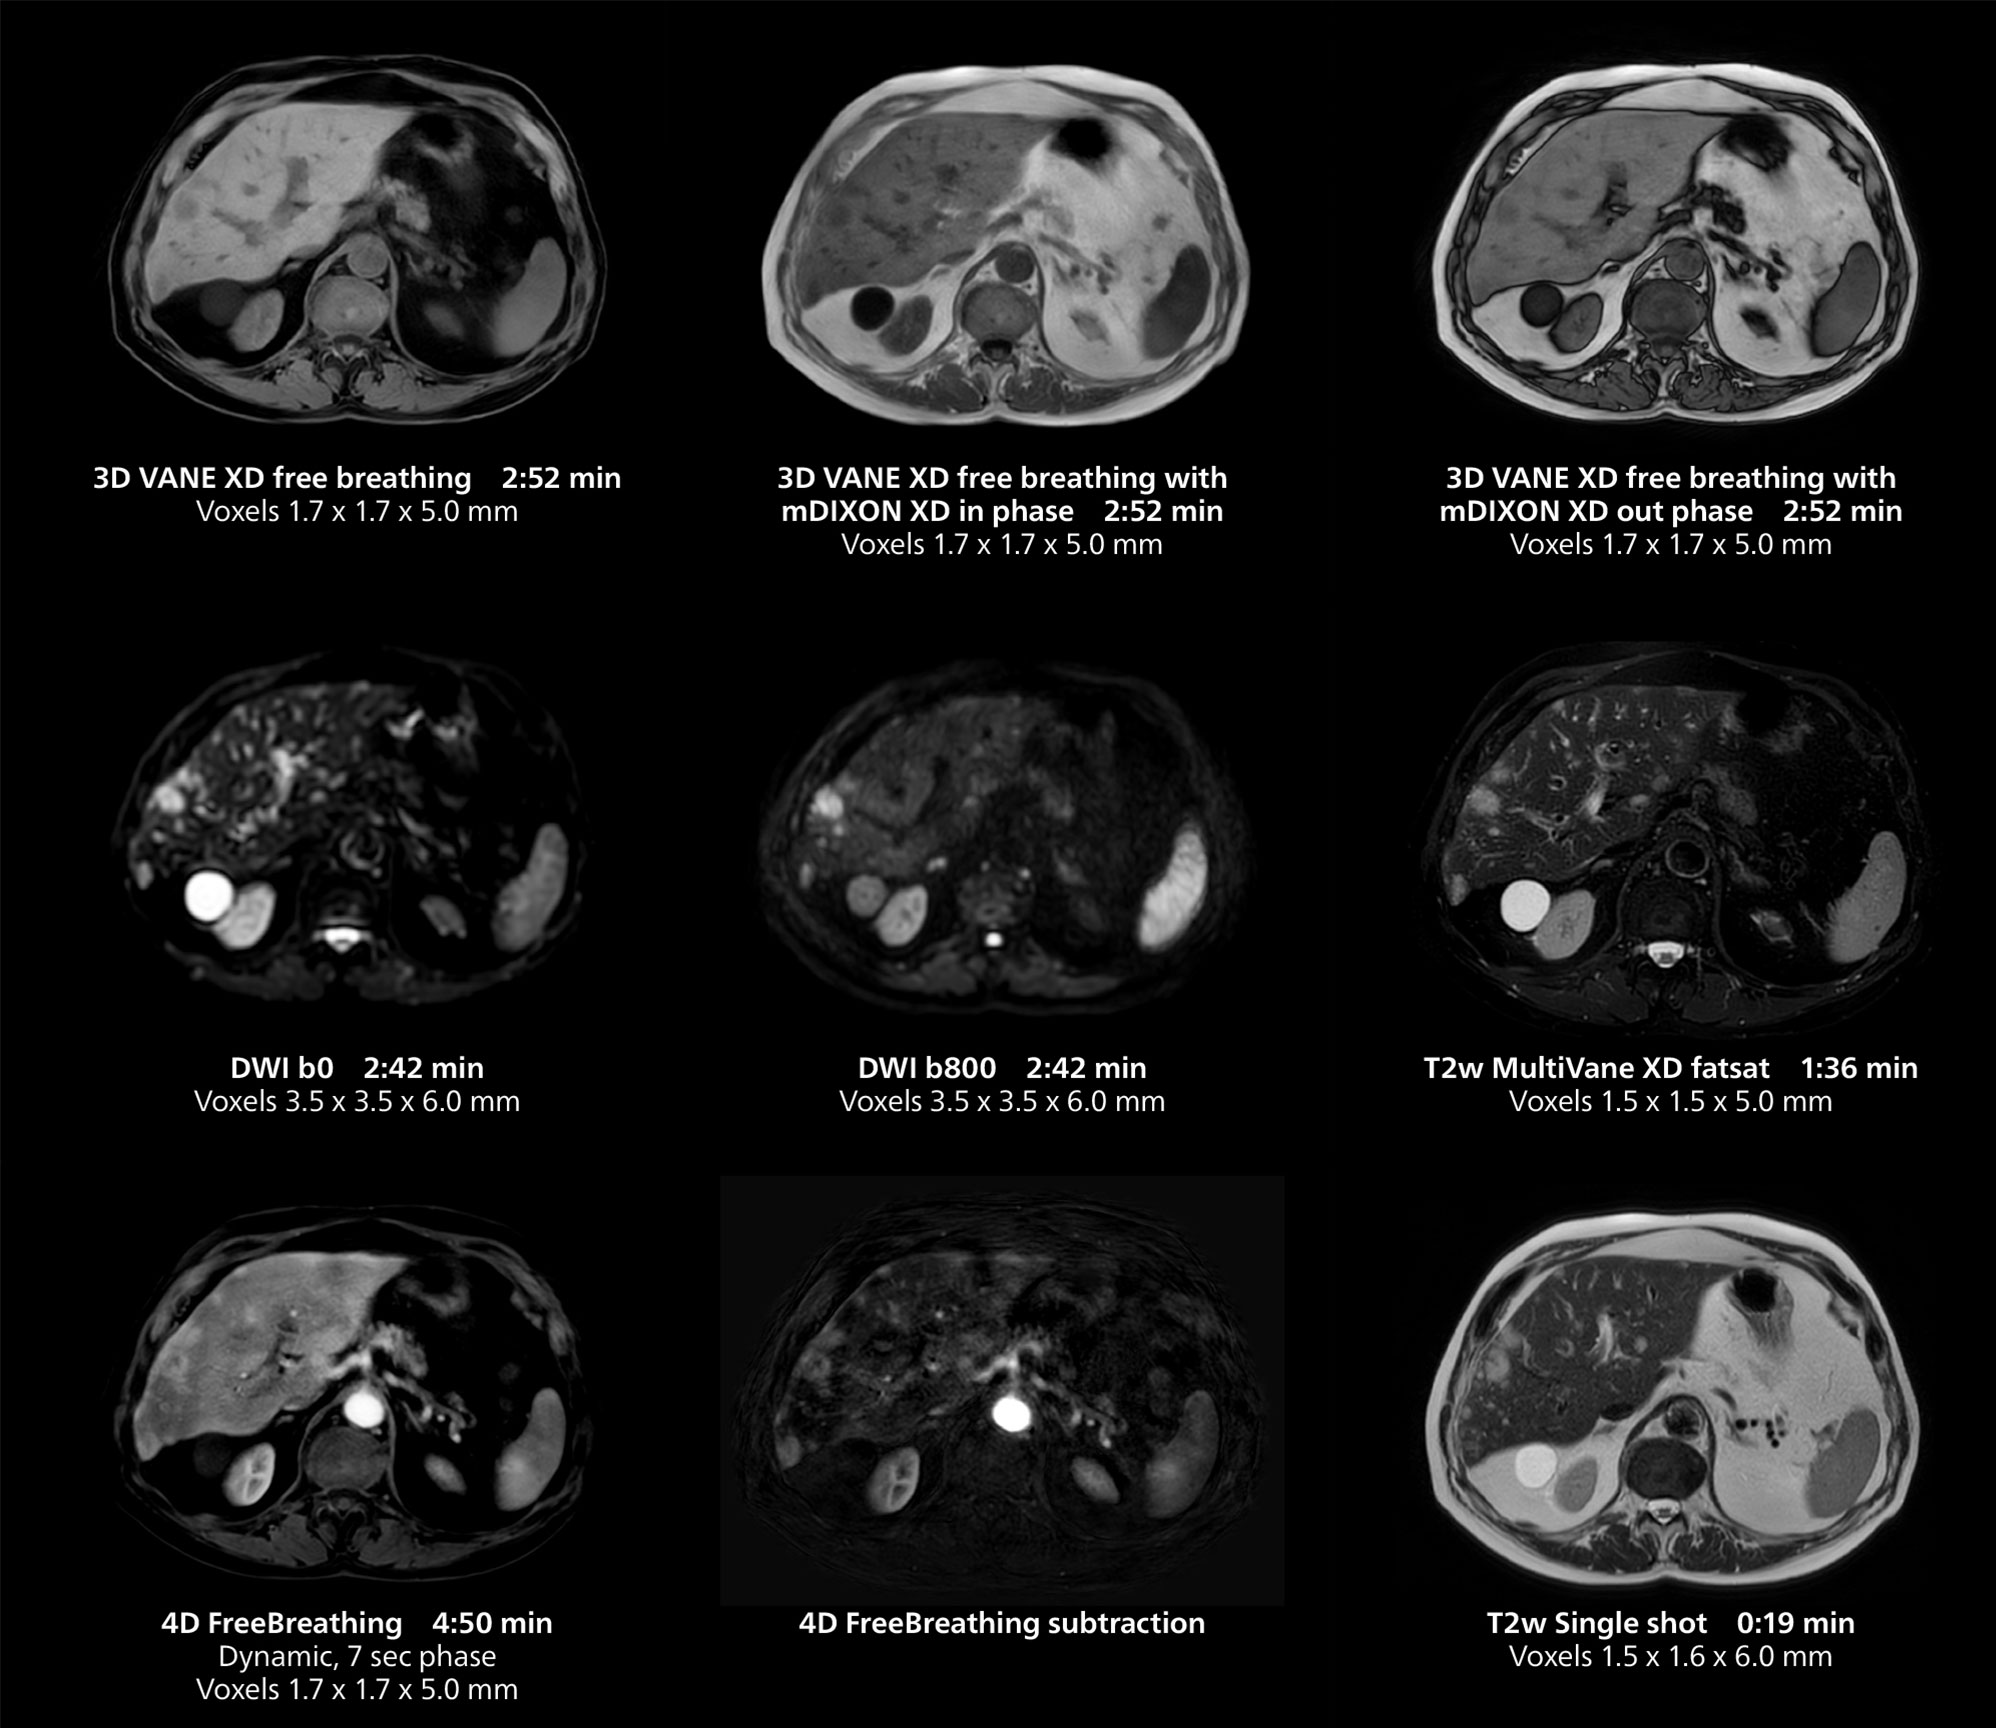

Le Dr Gellée estime que la fiabilité des acquisitions en respiration libre est “la caractéristique qui fait la plus grande différence au quotidien. Les séquences 3D en respiration libre sont très reproductibles et l’acquisition axiale est très bonne. Par exemple, pour l’endométriose, qui est l’un de mes domaines de prédilection, elles offrent un contraste élevé et une bonne résolution, ce qui me permet de voir les moindres détails. Nous utilisons également la respiration libre pour l’imagerie du foie et du pancréas. Dans les examens du foie multiphases, la respiration libre 4D offre une résolution temporelle de 3 secondes, permettant une acquisition dynamique avec plusieurs phases artérielles.”

Elle utilise également la respiration libre avec 3D mDIXON pour obtenir des images en phase, de l’eau et de la graisse en une seule acquisition. “Cette technique est très reproductible avant et après l’administration de gadolinium, ce qui la rend utile pour l’imagerie hépatique”, ajoute-t-elle.

Cet exemple comprend une IRM 3D en respiration libre et une IRM dynamique 4D en respiration libre d’un foie métastasé. Une séquence FatSat de haute qualité avec une bonne résolution est produite en 1 min et 36 s avec MultiVane XD pondéré en T2.

Cet exemple d’IRM illustre une bonne résolution et une bonne qualité d’image obtenue avec des temps d’acquisition raisonnables à l’aide du système MR 5300 1.5T avec l’antenne antérieure TorsoCardiac qui permet d’utiliser un champ d’acquisition étendu.